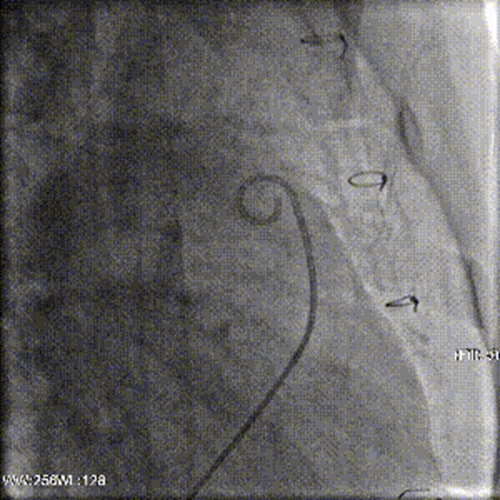

術(shù)前造影顯示肺動(dòng)脈瓣舒張期逆向血流